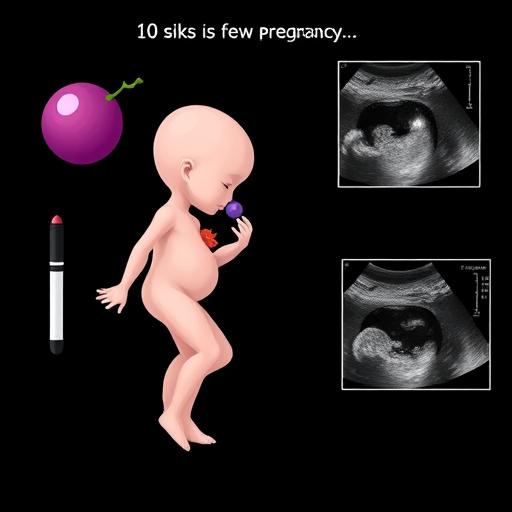

Визуальное представление плода

На 10 неделе беременности плод претерпевает удивительные изменения.

Длина: Плод достигает 3-4 см, сравним с крупной виноградиной.

Плод имеет пропорциональное тело. Головка крупная, глаза и уши формируются.

Ручки и ножки заметны, пальчики сформированы, но миниатюрны.

Внутренние органы функционируют. Сердце бьется около 160 ударов в минуту.

УЗИ показывает контуры тела, сердце, и даже движения.